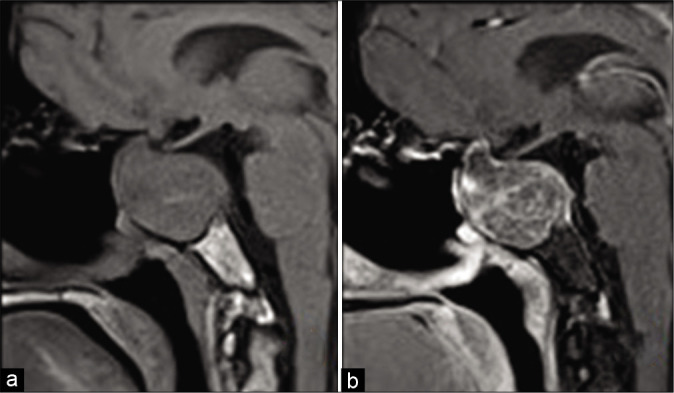

术后期间的临床再评估显示患者的视力和视野有明显好转。随访MRI显示视交叉和神经充分减压,尽管鞍内有大的残余病变[图4]。

图4:术后核磁共振图像。(a)矢状位对比前图像和(b)对比后T1加权图像,显示尽管存在较大残留鞍区海绵状血管瘤,但术后即刻的磁共振图像显示视神经充分减压